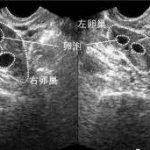

目前,海南省有8家医院可以开展辅助生殖技术,这其中只有1家医院可以开展第三代试管婴儿技术,它是海南医学院第一附属医院。该院的生殖医学中心成立于1993年,2002年通过卫生部批准可开展辅助生殖技术,于2019年4月胚胎植入前遗传学诊断技术正式运行。中心年门诊量达20万人次,目前IVF-ET临床妊娠率稳定维持在百分之50-65左右,为很多不孕不育夫妻带来了好孕。